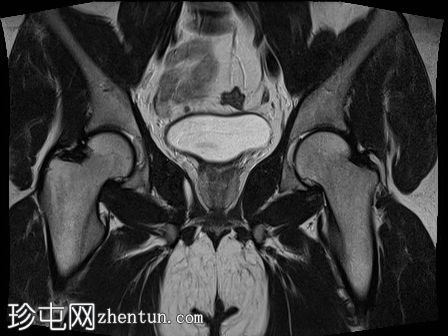

MRI

冠状位

T2加权像

1.jpg

双侧睾丸均未在阴囊内显露,而是位于盆腔腹股沟管上部。

-左侧睾丸大小为2.6 cm x 1.6 cm x 2 cm。

-右侧睾丸大小为2.6 cm x 1.2 cm x 1.1 cm。

双侧隐睾(睾丸未降)位于盆腔腹股沟管上部。